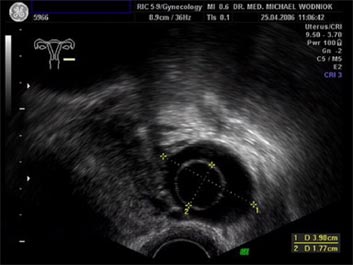

Hochauflösende Ultraschalluntersuchungen in Kombination mit der 3D-4D Technik werden in unserer Praxis routinemäßig durchgeführt. Dabei werden im Rahmen der Vorsorgeuntersuchung, sowie bei reinen vorsorglichen Ultraschalluntersuchungen auf Wunsch, auffällige Tastbefunde und noch unentdeckte Befunde weiter sonografisch abgeklärt. Bei zweifelhaften Befunden der Brüstdrüsen oder von Organen der inneren Genitalien kann der zusätzliche Einsatz der Farbdopplertechnik sehr hilfreich sein. Dabei stellt diese Technik bildlich sehr genau den Blutfluss, die Flussgeschwindigkeit, den Blutflusswiderstand sowie die Blutflussrichtung aller Blutgefässe dar. Die Interpretation dieser Ergebnisse fließt als zusätzlicher „Marker“ in die Entscheidung für das weitere klinische Vorgehen ein. Ein zunächst als völlig unauffällig eingestufter Ultraschallbefund eines zystischen Befundes im Eierstock wird bei einem unerwartet auffälligen Blutfluss an der inneren Zystenwand eine zeitnahe weitere Abklärung zu Folge haben. ![]() ![]() ![]()